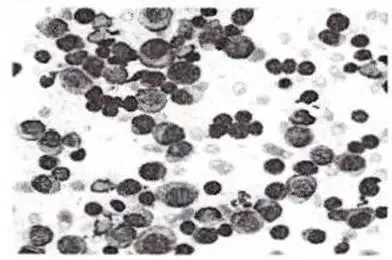

【单选题】92. 该患者血图片如下,最可能的诊断是()

A. 白血病

B. 多发性骨髓瘤

【单选题】93. 多发性骨髓瘤患者,外周血红细胞缗钱状排列,主要原因是

A.血液中钙离子增加

B.血膜涂片偏厚

C.严重脱水

D.纤维蛋白原增加

E.M蛋白增加